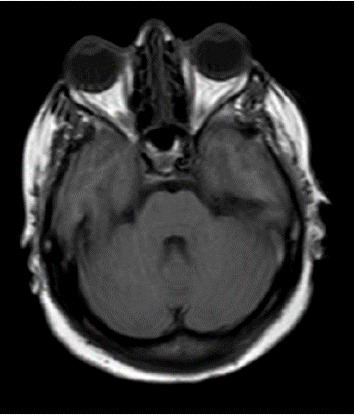

目的:探讨眼周填充物注射对脑静脉血栓形成(CVT)的影响。病例报告:一名没有既往病史的41岁女性在眼部填充物注射后出现严重头痛和随后的癫痫发作。通过脑磁共振静脉造影(MRV)证实CVT的诊断,显示左横窦和上矢状窦血栓形成。患者经静脉滴注肝素及口服华法林治疗,住院10天后病情好转出院。结论:本病例强调了眼周填充物注射后CVT的潜在风险,强调了医务人员认识和预防措施的必要性。

Purpose: To evaluate the effect of periocular filler injection on the incidence of cerebral venous thrombosis (CVT). Case Report: A 41-year-old woman without a prior medical history experienced a severe headache and subsequent seizures following an eye filler injection. Diagnosis of CVT was confirmed through brain magnetic resonance venography (MRV), revealing thrombosis in the left transverse and upper sagittal sinuses. The patient was treated with intravenous heparin and oral warfarin, leading to improvement and discharge in good condition after 10 days of hospitalization. Conclusion: This case underscores the potential risk of CVT following periocular filler injections, emphasizing the need for awareness and preventive measures among medical professionals.